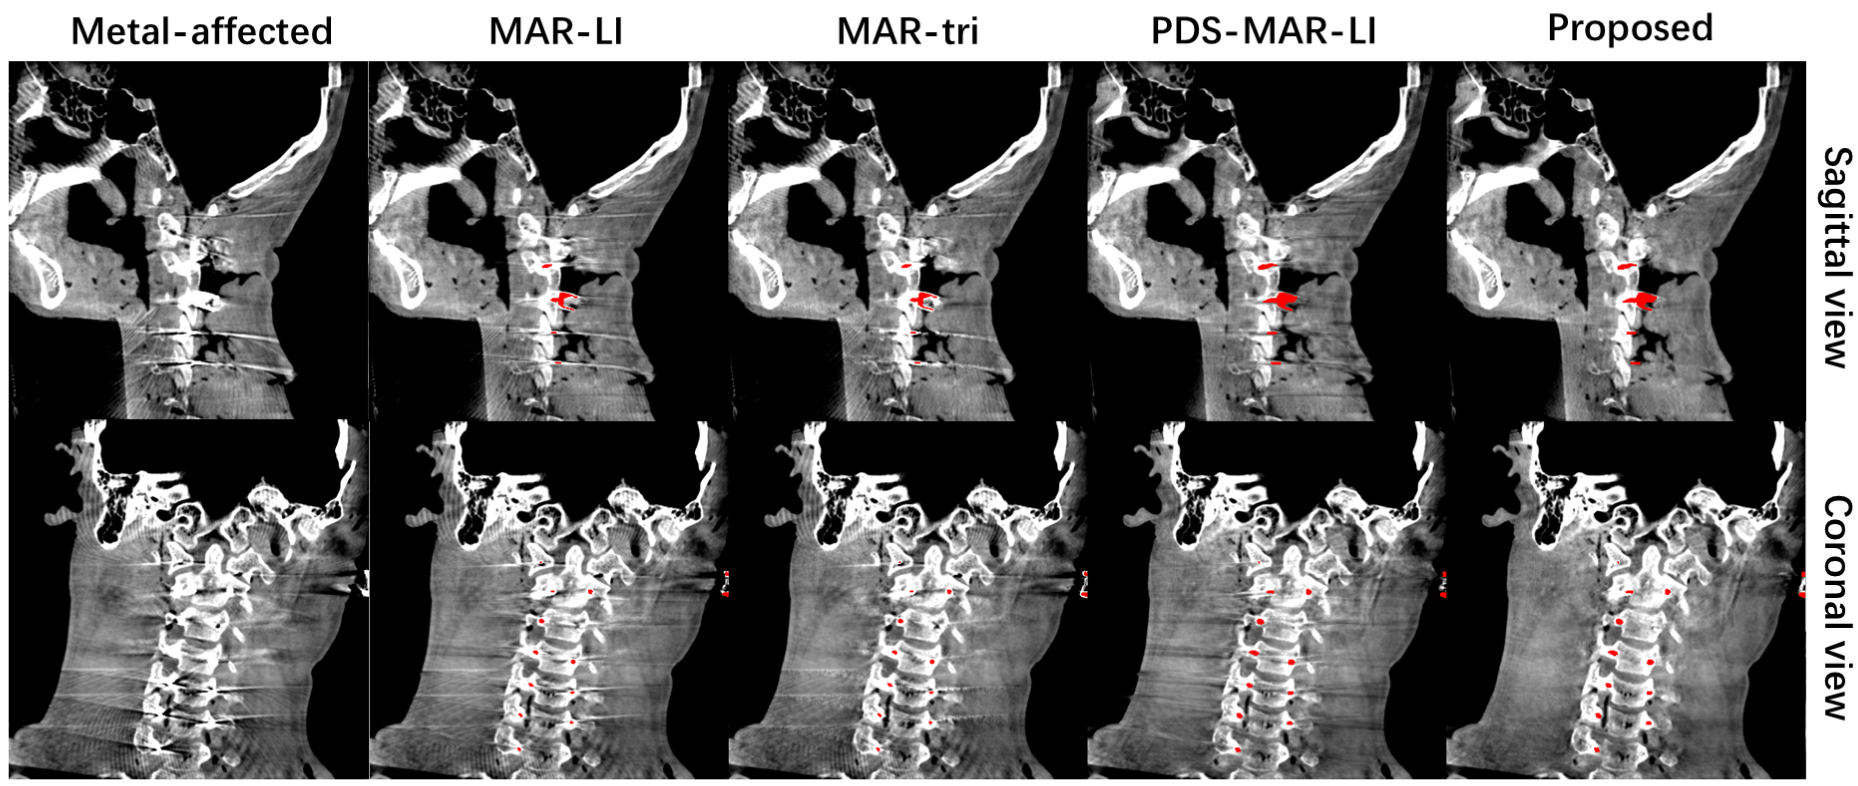

The reconstruction results for the head phantom are depicted in Fig. 9. These results reveal another shortcoming of image domain segmentation, namely the difficulty in threshold choice. Referring to Fig. 9 as an example, we compared results under (b-e) and (f-i) for different methods. Under a lower threshold, image domain methods can segment metal better. However, tooth regions are identified as metal objects due to their high attenuation properties, which introduce secondary (see Fig. 9 (b,c)). Under the higher threshold, tooth regions are not included; however, guidewires are not recognized and metal artifacts are not corrected. The proposed also suffers from segmentation faults on teeth under the threshold of 3000HU but performs well under the threshold of 6000HU. A slice in sagittal view and a slice in coronal view are displayed in Fig. 10. Besides guidewires, there are also metal screws inserted in the head phantom and the proposed algorithm can effectively deal with metal artifacts introduced by these screws.

The retention of precise metal masks in the image domain is another problem for MAR algorithms based on projection domain segmentation. In this paper, we propose a multiplicative-form backprojection-based metal mask reconstruction method that performs well on CBCT images with guidewires. Nonetheless, it does not completely resolve the issue. The projection domain masks lose information on the thicknesses of metal materials, making it impossible to retain hollow or concave metal masks. Two 2-D examples are presented in Fig. 13. In the projection domain, the solid circle and hollow ring have distinct characteristics, but when converted to binary masks, they yield the exact same result, as do the concave object and its minimal convex hull. In CBCT, the information in the z-direction weakens this problem (screws in Fig. 10), but it still presents on some slices (Fig. 9 (a5)). We are going to work in the future to incorporate metal thickness information into projection domain masks, which is the only way to solve this issue.